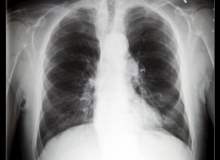

Akciğer Embolisi Teşhis Yöntemleri

Akciğer embolisinin teşhisi, özellikle arkasında kalp veya akciğerle ilgili bir rahatsızlık yatıyorsa zordur. Bu yüzden doktorunuz, belirtilerinizin nedenini bulmak için sizden bir dizi test yaptırmanızı isteyebilir.